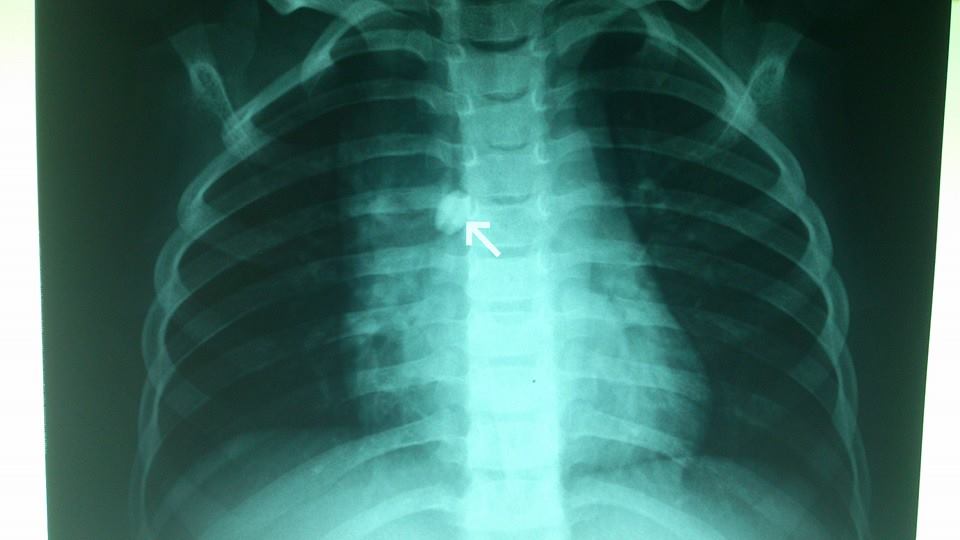

two years old male child came to our service with complain of sudden onset of dry irritant cough. clinical examination demonstrate decrease air entry on the right side. chest X ray show a foreign body in the right main bronchus and a tunnel inside the FB. using Fogerty catheter inserting its tip inside the tunnel then inflate the balloon distal to FB and gentle withdrawal of the whole bronchoscopy system with it.

rosary beads is not uncommon foreign body to be aspirated in Egypt. the common problem arise as the edges of this FB is smooth with slipping edges and the size of it relative to child bronchus is big . that's why it become difficult to extract with usual bronchoscopic forcepes as no enough space to insert the forecepes around it and difficulty to catch its slipping edges. using the tunnel inside the beads to insert a Fogarty catheter then inflate the balloon and gentle withdrawal of the bronchoscopy system as one unit is an alternative apporach for this difficult FB to prevent patient from undergo an open bronchotomy to remove it.